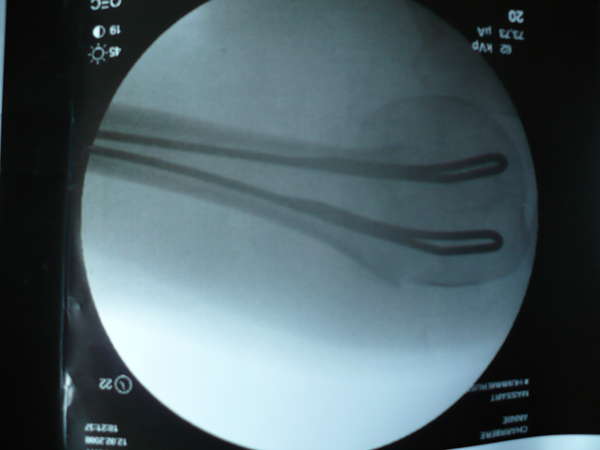

L'épaule d'Annie a été consolidée par deux broches passées par le coude. L'humérus est désormais réparé, la rééducation peut débuter.

Hier mardi Annie a consulté un spécialiste à Chambéry pour son épaule. Nous avons été d'accord pour une intervention immédiate: elle a été opérée tout de suite et possède désormais 2 belles broches de métal dans l'humérus. Elle a aujourd'hui un peu mal mais la rééducation a déjà débuté: elle pourra bientôt à nouveau pédaler!

Annie est sortie de la clinique chambérienne le jeudi 14 février avec 2 belles broches dans l'humérus. Elle va pour le mieux, ne souffre qu'à l'occasion d'un faux mouvement, et se décharge volontiers des taches ménagères que j'assume avec courage.